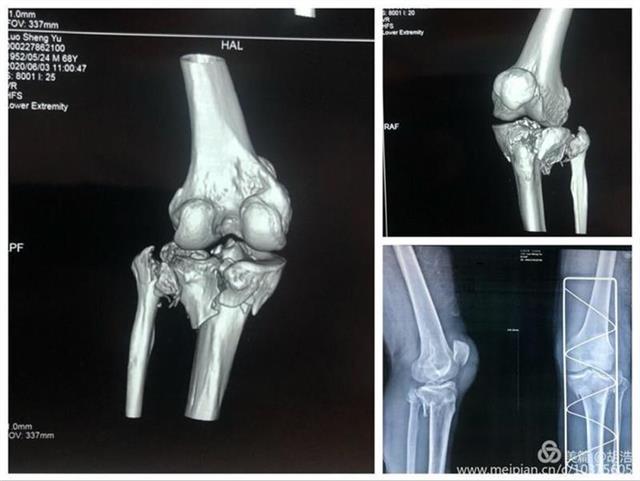

数字化设计结合3D打印技术,打印出了受损的胫骨、腓骨、股骨模型。在杨俊忠带领下骨科创伤关节专家组成员副主任医师胡浩、副主任熊家亭、医师黄攀、黄传文进行了术前的讨论,根据模型精准了解骨折类型,设计手术切口、预演术中步骤、内植物的安放位置及术中复位技巧,制定出可行的治疗方案,手术按照计划进行,术后的康复也令人满意。